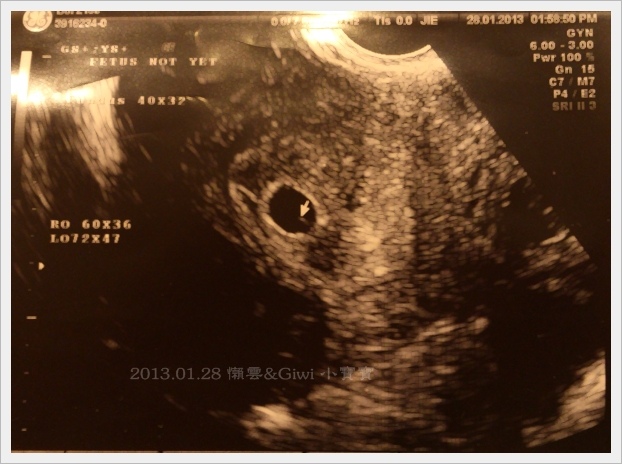

今天要做陰道超音波, 檢查時有點小緊張, 不知道小傢伙有沒有在子宮裡好好待著!! 本來檢驗師在照時說有照到一顆, 沒過多久居然說還有一顆….@@~

檢驗師 : , 現在看到的黑圈圈裡有點白白的叫卵黃囊, 那是供給寶寶12週前的營養所需

檢驗師 : 週數還太小, 還不能確認, 若到時都有住人就是雙胞胎了

後來醫生問診時, 也說了目前位置及大小都很正常, 叫我們約一週半後再去照一次超音波, 這時應該要照到心跳了才對…..